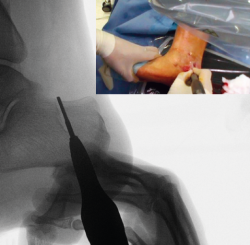

Osteosíntesis

Una vez comprobado el suficiente desplazamiento en la proyección axial del calcáneo, se fija la osteotomía con 2 agujas de Kirschner sobre las que se introducirán 2 tornillos canulados de un tamaño de entre 5,5 y 7 mm, y se verifica su correcta colocación en la visión lateral y axial fluoroscópica (Figura 9).

Figura 9. Imágenes fluoroscópicas de fijación de la osteotomía con agujas de Kirschner y tornillos canulados en anteroposterior y axial del calcáneo.